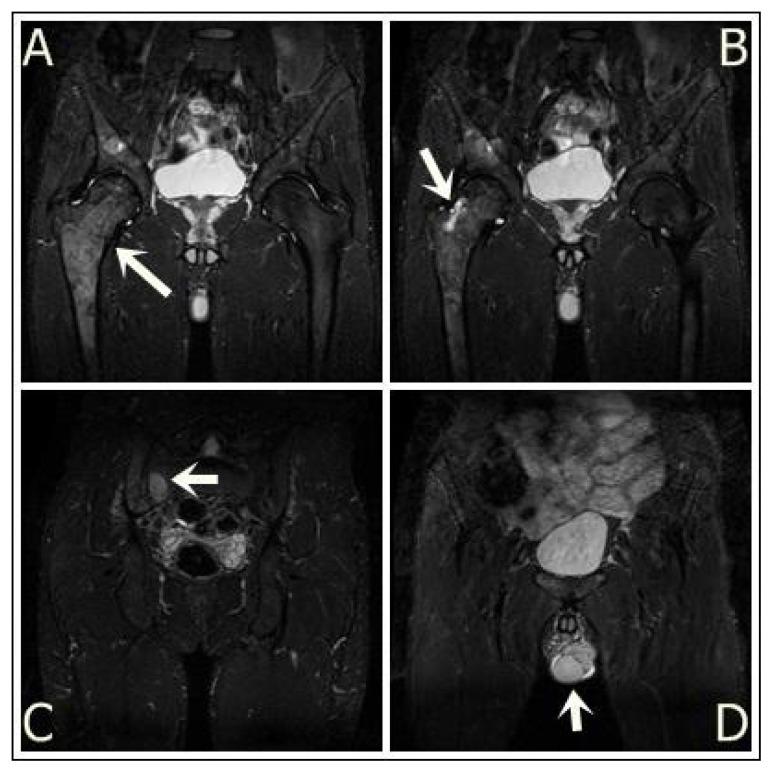

McCune-Albright syndrome is a rare sporadic disease characterized by bone fibrous dysplasia, café-au-lait skin spots and a variable association of hyperfunctional endocrine disorders. Fibrous dysplasia (FD), which can involve the craniofacial, axial, and appendicular skeleton, may range from an isolated, asymptomatic monostotic lesion to a severe disabling polyostotic disease involving the entire skeleton. A twenty-five-year old male patient presented to our clinic with recently developed heart palpitations. He had also been feeling pain in the right femur since he was younger, without any trauma history, leading to difficulties of ambulation and limping occasionally. His physical examination revealed café-au-lait spots with irregular borders and right testicular agenesis. Laboratory findings identified hyperthyroidism with hyperparathyroidism. Radiographs of the pelvis revealed multiple lytic lesions of the right femur and magnetic resonance imaging (MRI) characterized these lesions as specific to fibrous dysplasia of the bone, without any insufficiency fracture at this level. The association of café-au-lait skin spots with bone fibrous dysplasia, and hyperthyroidism in this patient suggested the diagnosis of McCune - Albright syndrome.

McCune - Albright综合征是一种罕见的散发性疾病,其特征为骨纤维发育不良、咖啡斑皮肤斑点以及多种功能性内分泌紊乱。纤维发育不良(FD)可累及颅面骨、中轴骨和四肢骨骼,范围从孤立的无症状单骨病变到累及整个骨骼的严重致残性多骨疾病。一名25岁男性患者因近期出现心悸前来我院就诊。他自幼右股骨就一直疼痛,无任何外伤史,导致行走困难且偶尔跛行。体格检查发现边界不规则的咖啡斑以及右侧睾丸发育不全。实验室检查结果显示患有甲状腺功能亢进和甲状旁腺功能亢进。骨盆X线片显示右股骨有多个溶骨性病变,磁共振成像(MRI)将这些病变特征化为特定的骨纤维发育不良,在此层面无任何应力性骨折。该患者咖啡斑皮肤斑点与骨纤维发育不良及甲状腺功能亢进的关联提示了McCune - Albright综合征的诊断。